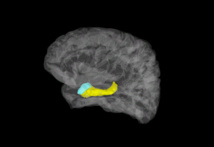

Imagen cerebral en la que aparecen coloreadas la amígdala (azul) y el hipocampo (amarillo). Imagen: Stephan Moratti. Fuente: UPM.